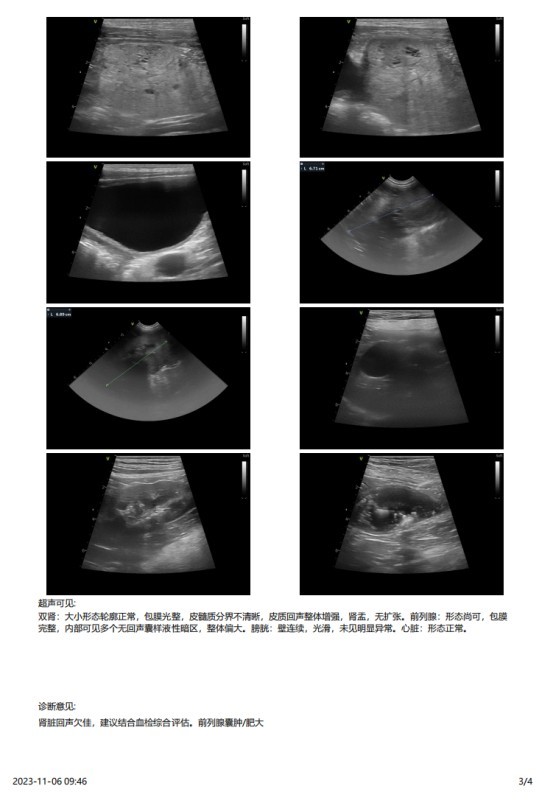

主诉最近发现两只睾丸的大小相差较大,精神状态尚可,挑食。于近日入院进行病变部位的超声检查,结果如图:

该图为肿大的左侧睾丸

2023 年 3 月份检查结果

肿物切面:黄棕色,质软,切面隆起。它们通常含有出血和 / 或囊肿。这些表现跟临床超声的怀疑囊性的结果一致。